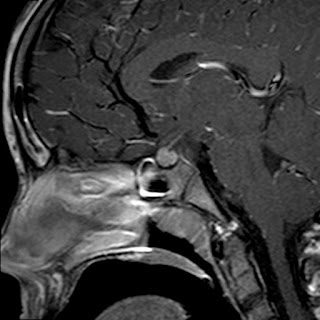

Caso neurorradiología

Paciente de 60 años con cuadro de 1 semana de evolución consistente en tropiezos frecuentes y alteración en la movilidad del miembro

inferior derecho. No refiere

cefalea u otros síntomas asociados, no pérdida de peso, no náuseas o emesis, no

sudoración nocturna. Antecedentes de hipertensión arterial y diabetes.

Resonancia magnética